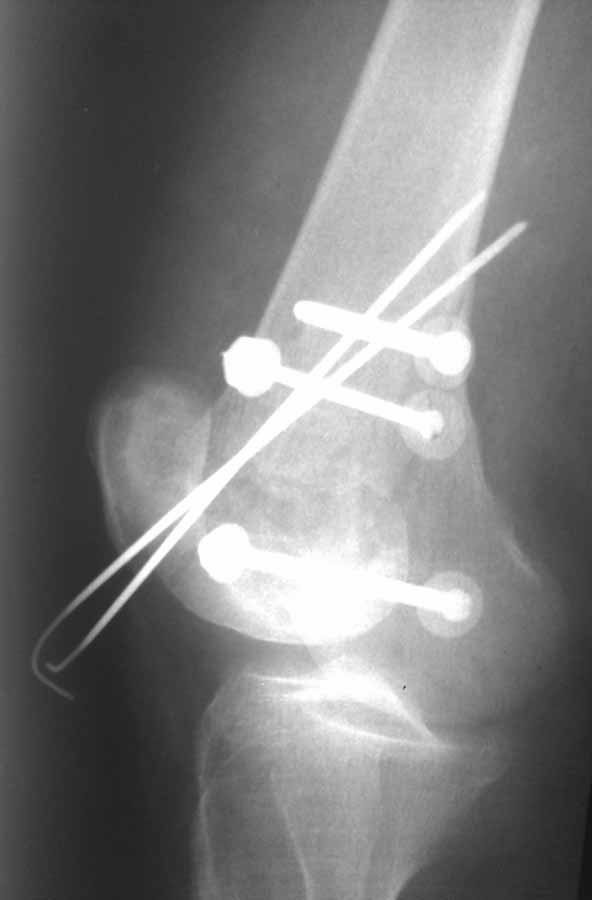

Ну зачем же так. Всё-таки считается "золотым стандартом". Во вложенном файле коллаж из сохранившихся фотографий одной из операций. Всё сделано закрыто и без ЭОПа.

Ответ на эту часть Вашего поста – вложенный файл. Больная оперирована неделю назад по поводу открытого перелома дистального эпиметафиза бедренной кости. После операции она идёт в рентгенкабинет для выполнения послеоперационной контрольной рентгенографии, представленной на слайдах 10 и 11. Узнав, почему её фотографируют, просила передать Вам, Антон, привет.

По прямому снимку репозиция удалось, поздравляю! А с латеральной стороны подозрение на флексионный компонент латерального мыщелка остается, а снимок получился косым, надо было бы повторить.

Выбор имплантов не совсем удачный, подкожно выступающие болты в мыщелках вскоре могут привести к проблемам. Вместо солитарной фиксации болтом-стяжкой дистально можно было бы добавить пару винтов, которые создали бы ротационную стабильность и межфрагментарную компрессию.

Возможно, есть скрытый замысел, неочевидный для нас - не понятны латерально оставленные спицы. Спицы возможный очаг вторичного осложнения, и, тем более у взрослых, тонкие спицы не создают адекватную фиксацию.

Djoldas,скрытого смысла в спицах нет. Без них латеральный мыщелок получается фиксированным только к медиальному, который, в свою очередь, фиксирован к проксимальному отломку. Соответственно латеральный мыщелок не фиксирован к бедру. Спицами мы попытались создать какую-никакую-стабильность латерального мыщелка относительно проксимального отломка бедра.

Болт-стяжка, на мой взгляд, создает не меньшую межфрагментарную компрессию чем винты. Не понял относительно ротационной стабильности винтов.